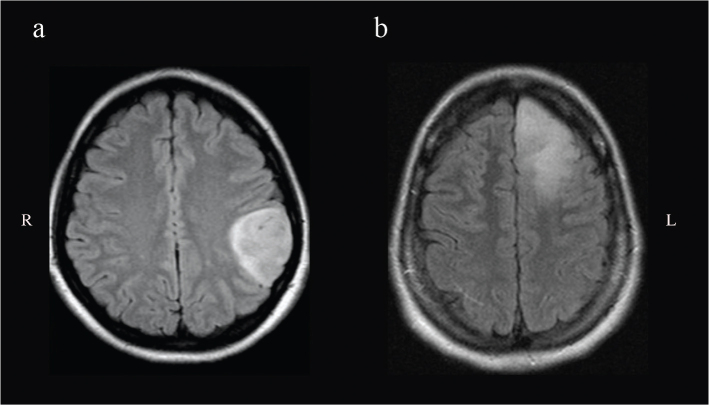

Methods: A series of confirmed WHO 2 astrocytoma patients (between 2005 and 2015) were retrospectively analyzed. MRI sequences (FLAIR) were used for tumor volume segmentation and to create a frequency map of their locations into the Montreal Neurological Institute (MNI) space. The Brain-Grid (BG) system (standardized radiological tool of intersected lines according to anatomical landmarks) was used as an overlay for infiltration analysis of each tumor. Long-term follow-up was used to perform a survival analysis.

Results: Forty patients with confirmed IDH status (26 IDH-mutant, IDHm/14 IDH-wild type, IDHwt) according to WHO 2021 classification were included with a mean follow-up of 7.8 years. IDHm astrocytomas displayed a lower number of BG-voxels (P < 0.05) and were preferentially located in the anterior insular region. IDHwt group displayed a posterior insular and peritrigonal location. IDHwt group displayed a shorter OS compared with IDHm (P < 0.05), with the infiltration of 7 or more BG-voxels as an independent factor predicting a shorter OS.

Conclusions: IDHm and IDHwt astrocytomas differed in preferential location, number of BG-voxels and OS at long follow-up time. The number of BG-voxels affected the OS in IDHwt was possibly reflecting higher tumor invasiveness. We encourage the systematic use of alternative observational tools, such as gradient maps and the Brain-Grid analysis, to better detect differences of tumor invasiveness in diffuse low-grade gliomas subtypes.